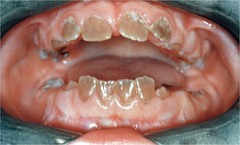

Meth mouth

Front

-generalized extensive destruction of tooth surface -meth use